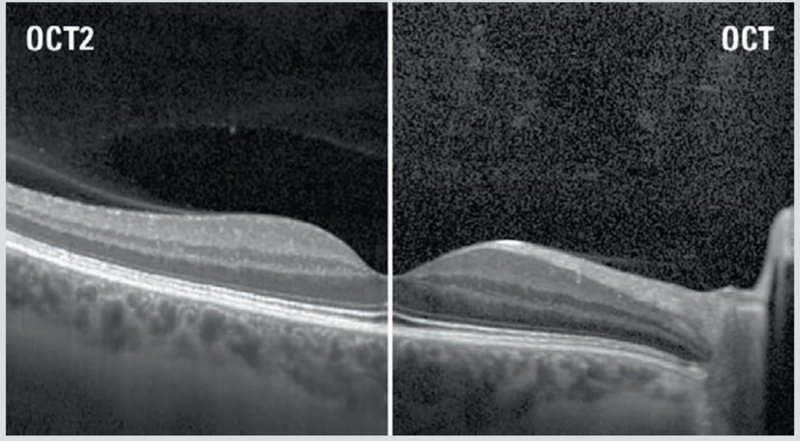

The ZEISS Cirrus HD-OCT 4000 (Cirrus HD-OCT or Cirrus) enable examination of the posterior and anterior of the eye at an extremely fine spatial scale, without surgical biopsy or even any contact with the eye. The Cirrus HD-OCT builds on and refines the retinal imaging technology first introduced with the ZEISS Stratus OCT HD-OCT stands for "high-definition optical coherence tomography."